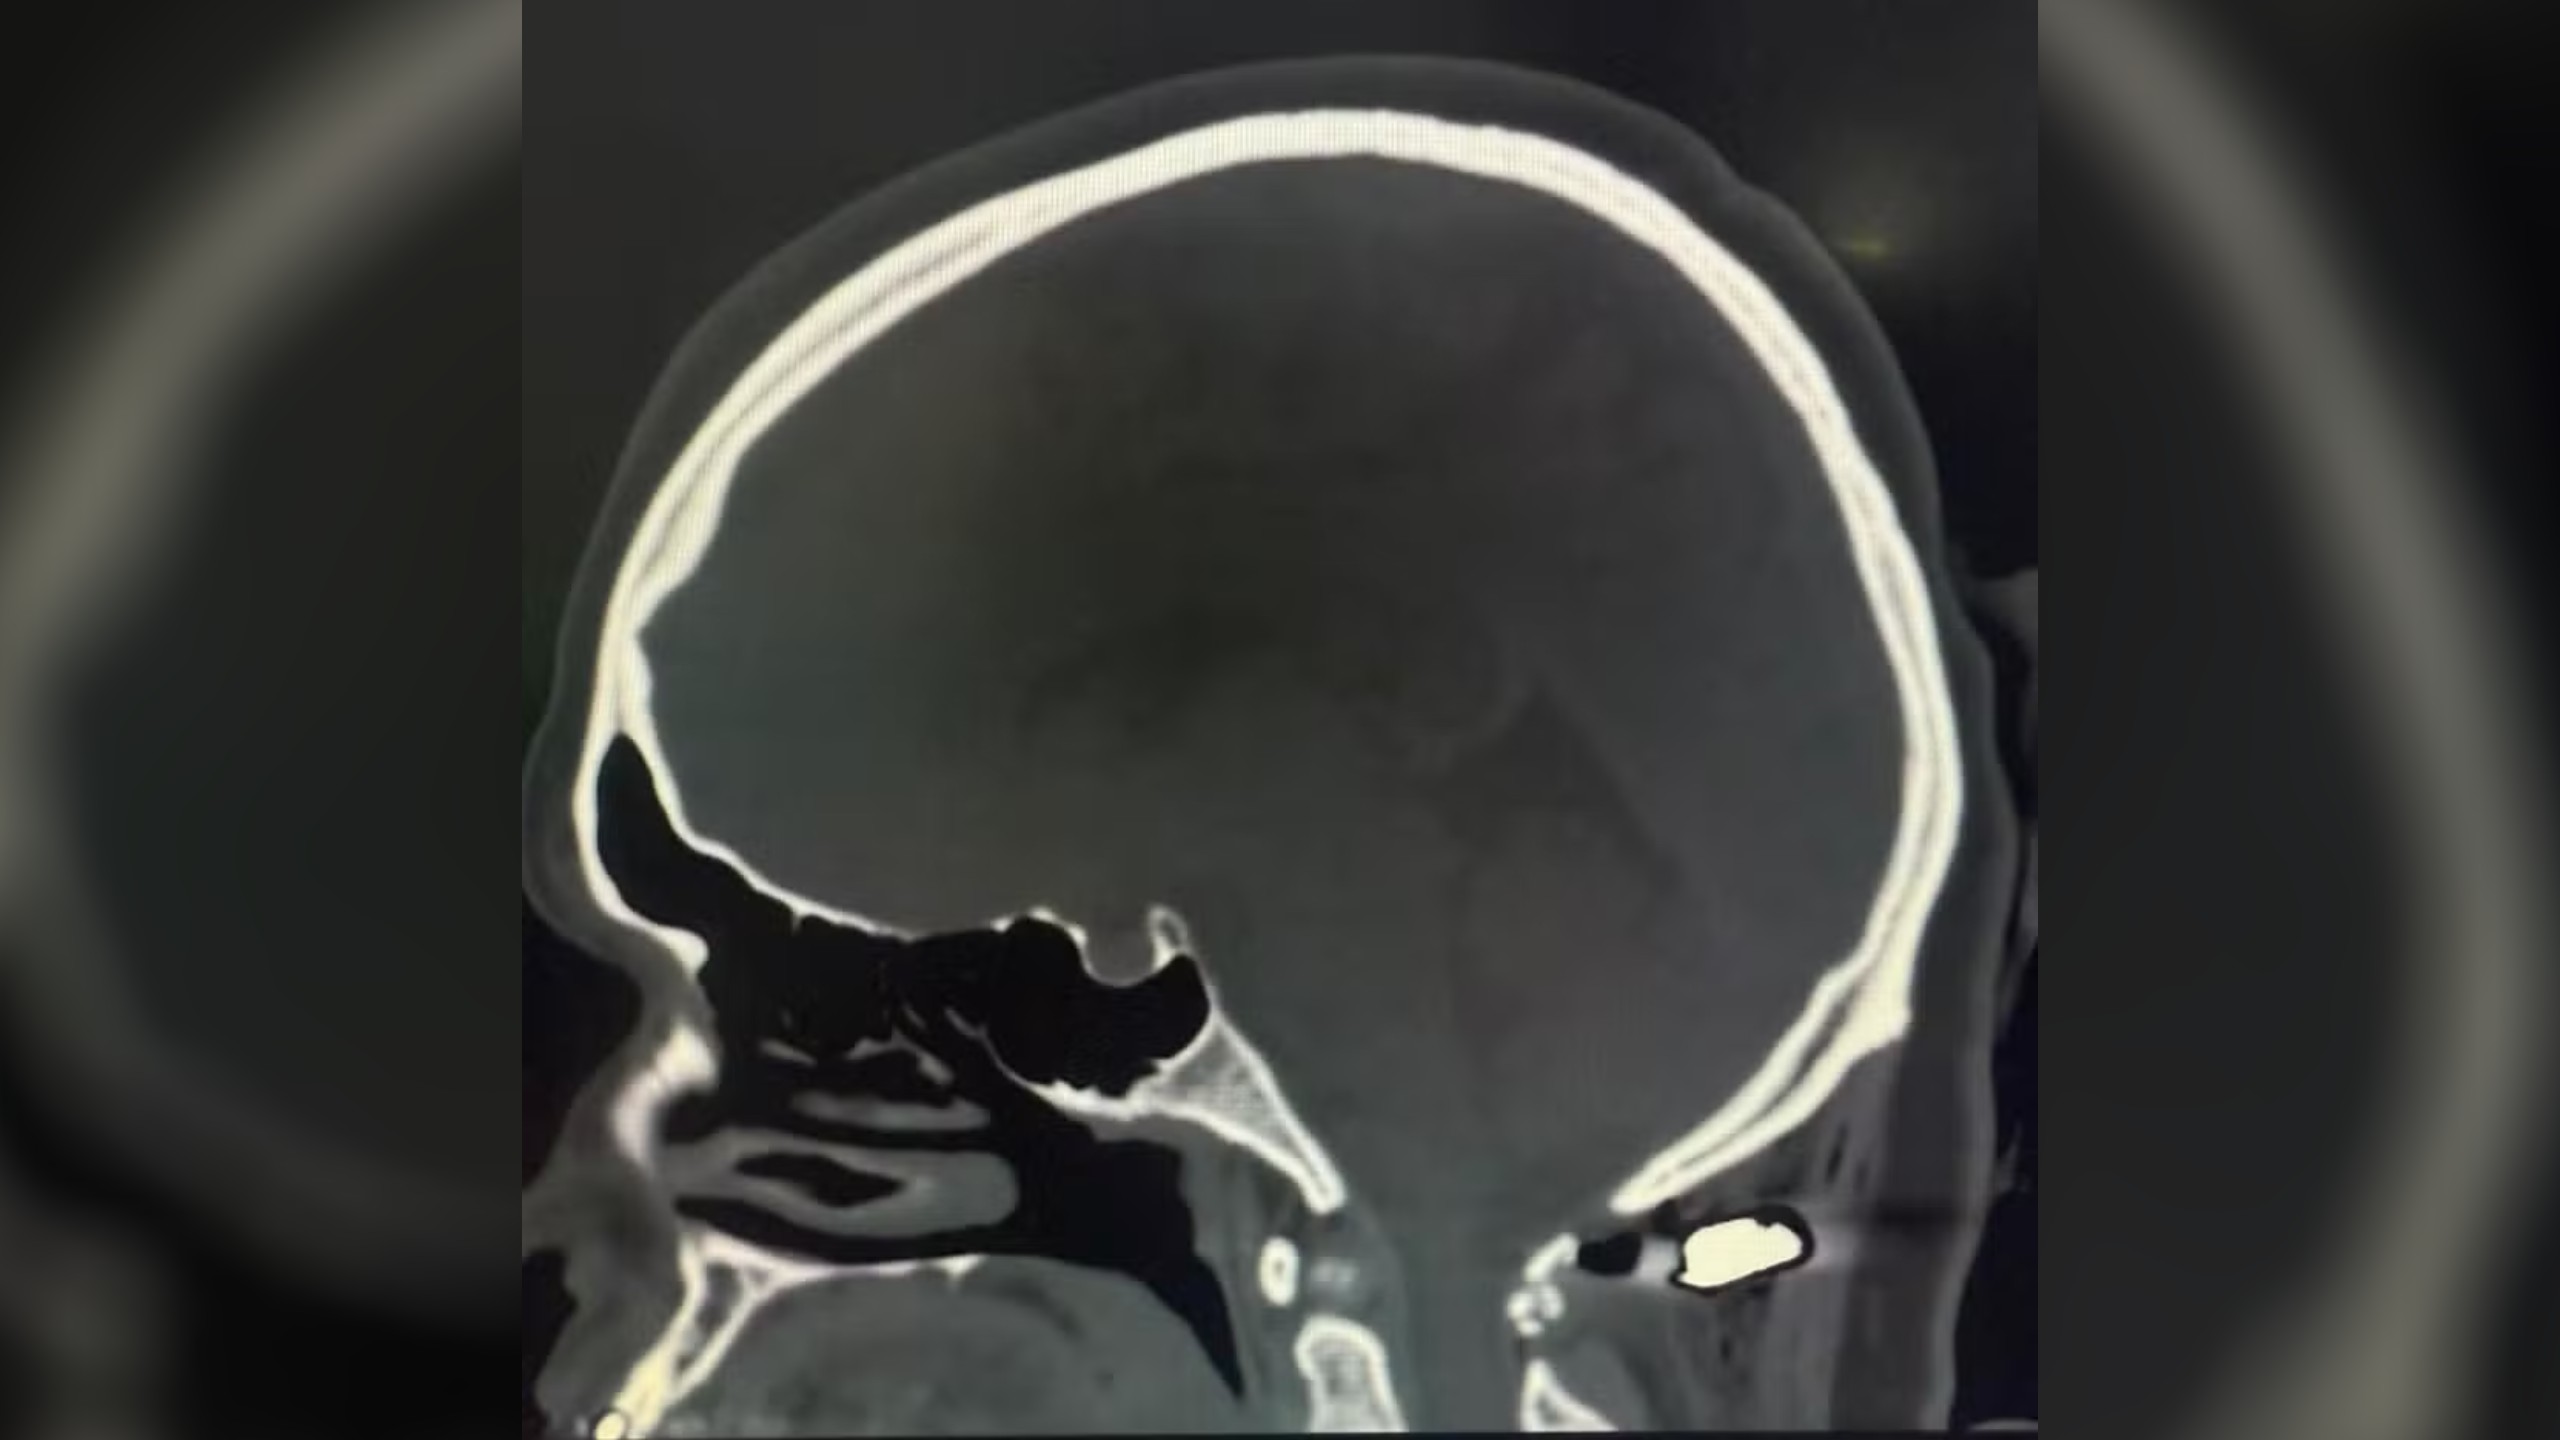

Intoxicação por metanol: Brasil tem 47 casos confirmados, diz ministério

O que acontece no corpo nas primeiras 12, 24 e 48 horas após beber metanol O Ministério da Saúde divulgou nesta segunda-feira (20) uma nova atualização sob